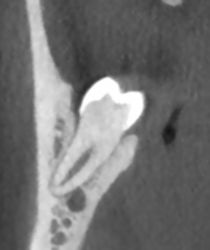

Qu'est ce qu'un Conebeam ?

En quoi consiste l'examen ?

C'est un examen qui est demandé dans les problèmes dentaires, avant une pose d'implant.

L'appareil effectue une rotation autour de vous pour acquérir toute l'arcade dentaire et pour être en mesure de reconstruire les images dans tous les plans de l'espace (3D).

• Une résolution optimale

Longtemps, le scanner était privilégié pour l'étude 3D des massifs dentaires; la technique Conebeam offre aujourd'hui une résolution supérieure au scanner pour ce type d'examen, avec en plus l'avantage de délivrer une dose très faible.